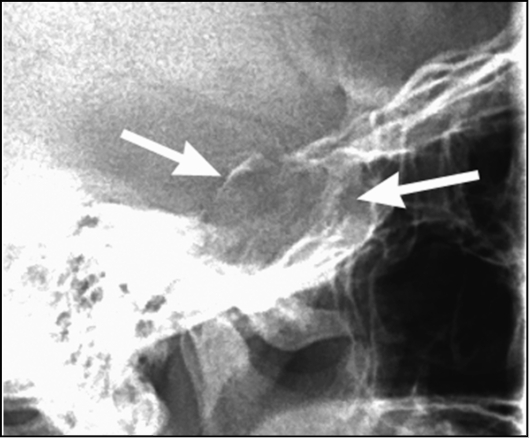

Рентген турецкого седла показания противопоказания методика проведения Автор Екатерина Михайлюк | дата обновления 09.01.2017Мой мирВконтактеОдноклассники Рубрика: Поделись в соцсетяхВконтактеОдноклассники